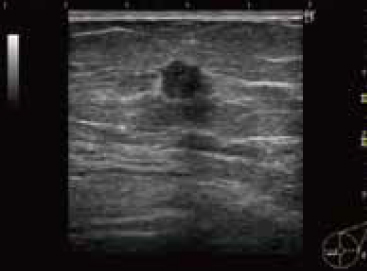

Breast Cancer

低亮度的部分图像区域中边界与内部的图像是不规则的

Irregularities were found in the outer and internal sections with low-intensity, localized images